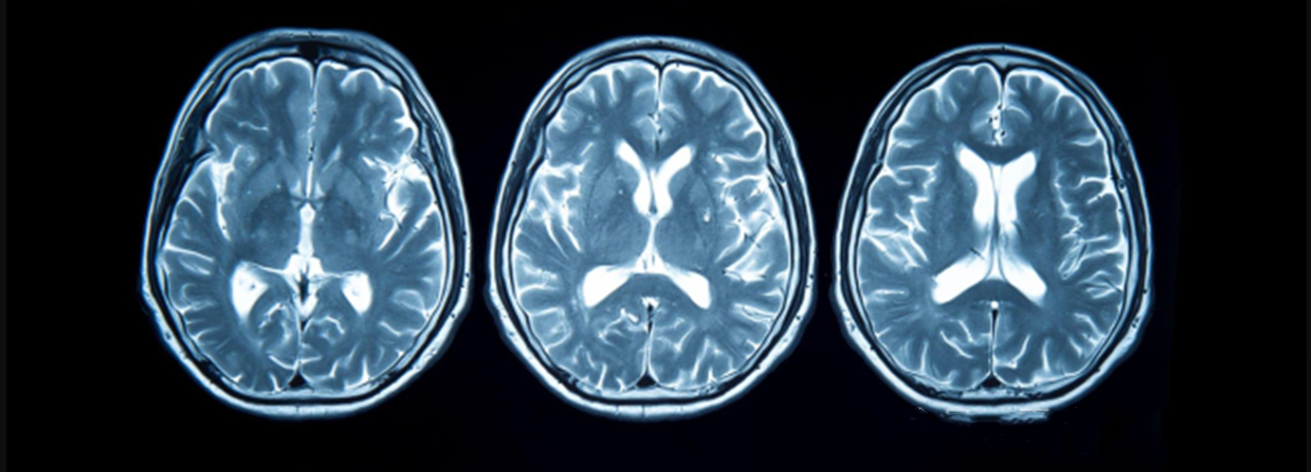

創(chuàng)傷性腦損傷(TBI)是一種由外力導(dǎo)致的腦部損傷及功能障礙,是一種異質(zhì)性疾病。在多重機(jī)制作用下,TBI患者的致殘率和病死率較高,給家庭和社會帶來沉重負(fù)擔(dān)。TBI的臨床治療多以外科手術(shù)及減輕腦缺氧、腦水腫和代謝紊亂等對癥治療為主。近年來,干細(xì)胞逐漸成為TBI治療的研究熱點(diǎn)之一。

圖片:來源于網(wǎng)絡(luò)